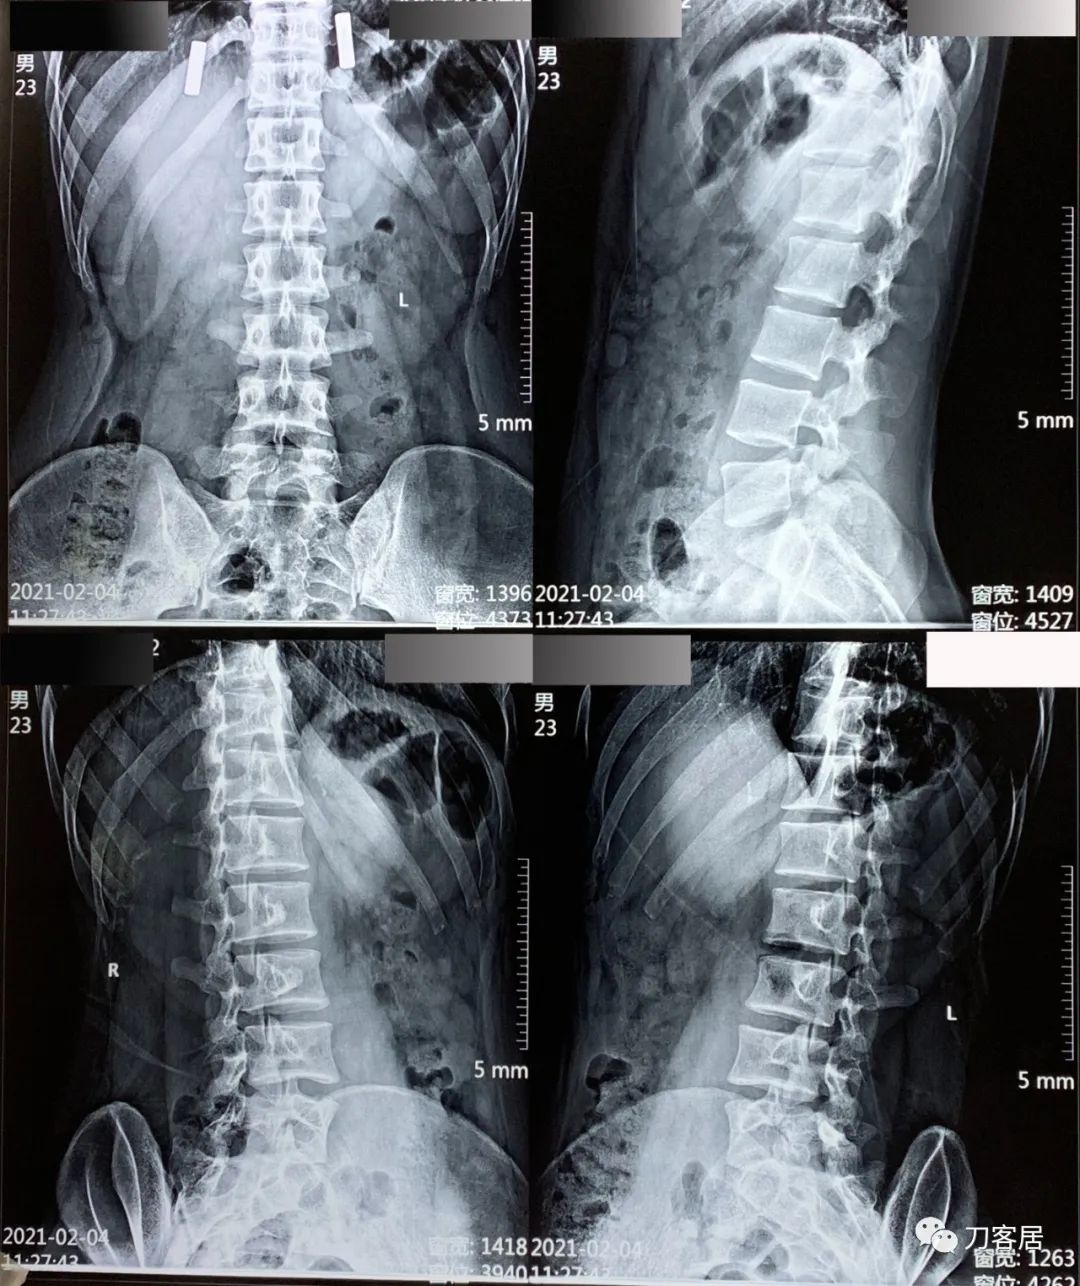

图1. 20210204外院院腰椎正侧位及双斜位X线片。

自带腰椎X线片提示右侧峡部裂,外院CT报告右侧腰5峡部裂,腰5骶1隐裂。腰椎MRI及CT检查未见椎间盘突出及椎管狭窄,